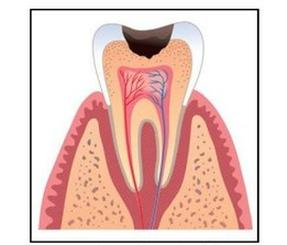

Zmianę widoczną na rysunku, w klasyfikacji próchnicy ze względu na zaawansowanie zmian, oznacza się jako

A. D2

B. D4

C. D3

D. D1